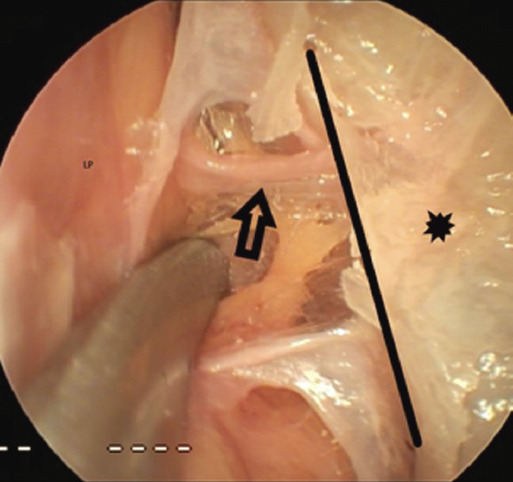

Method: Five fresh frozen cadaveric heads underwent computed tomography and endoscopic sinus surgery. The lateromedial length of the anterior ethmoidal artery (AEA) and its distance to the axilla of the middle turbinate (MTA), the sphenoethmoidal recess (SR) and the posterior ethmoidal artery were measured. The posterior ethmoidal artery (PEA) was referenced to the SR. These anatomical parameters were measured both radiologically and endoscopically, and the compatibility of the two was examined.

Results: Ten nasal cavities were dissected. We found that the distance of MTA to the AEA was 16±8 mm in dissection, 21±4 mm radiologically in the sagittal section, the distance of SR to the AEA was 14±3 mm in dissection, 19±4 mm radiologically in the sagittal section, and the distance of the AEA to the PEA was 10±3 mm in dissection, 12±3 mm radiologically in the axial section. The distance of the PEA to SR was 6±3 mm in dissection, 8±2 mm radiologically in the sagittal section.